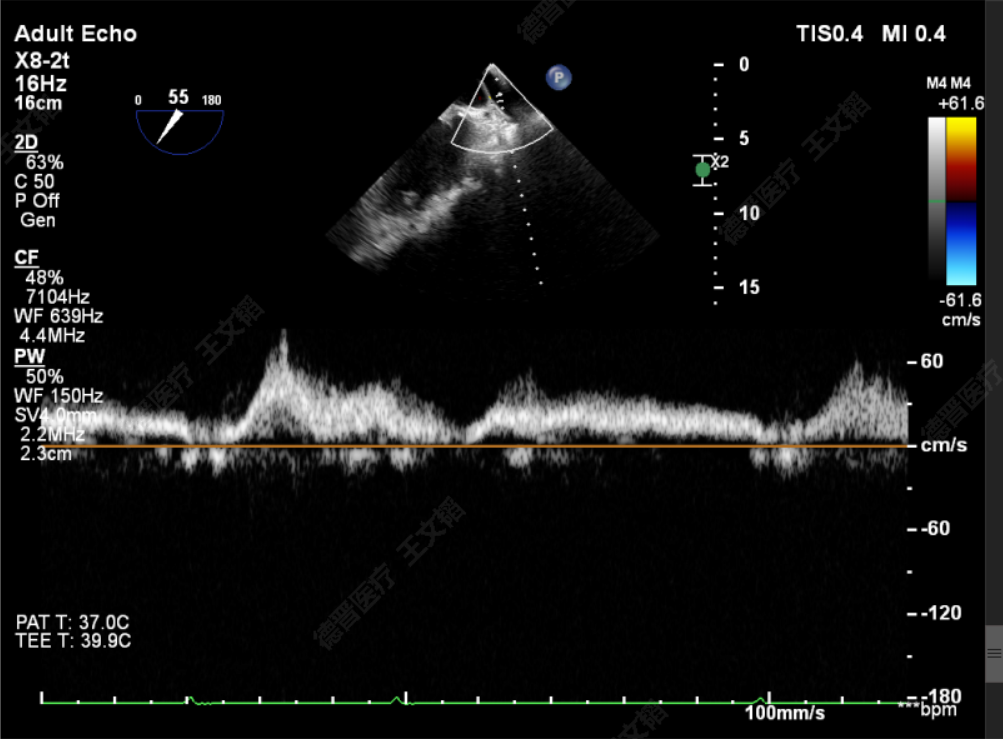

两枚夹子中间有残余反流1+

解离后3D评估组织桥稳定

反流未增加